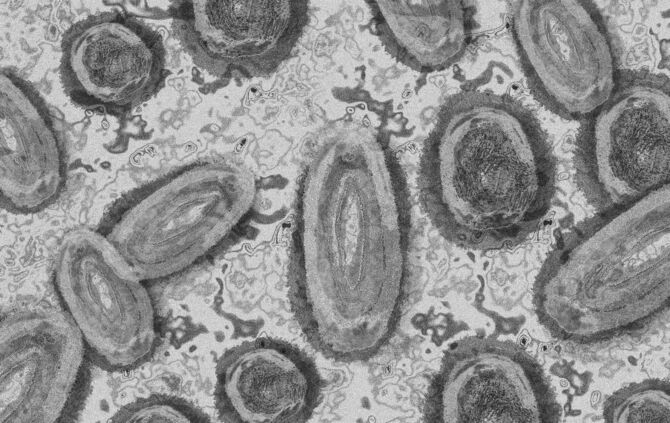

Jetzt auch Affenpocken im Rems-Murr-Kreis: Was wir über die drei bekannten Fälle wissen

Seit dem Wochenende gibt es die ersten bestätigten Fälle von Affenpocken im Rems-Murr-Kreis: Drei Männer befinden sich in häuslicher Isolation. Das geht aus einer Pressemitteilung des Landratsamtes hervor.

Affenpocken sind eine seltene, von Tieren, vermutlich vor allem Nagetieren, auf Menschen übertragbare Viruserkrankung. Übertragungen von Mensch zu Mensch sind selten, aber möglich, vor allem bei sehr engem Kontakt. Affenpockenviren sind in West- und Zentralafrika bei Nagetieren verbreitet.

Menschen können sich vor allem durch Kontakt mit den Hauteffloreszenzen, Blut, Gewebe oder Ausscheidungen infizierter Tiere (in erster Linie verschiedener Nagetiere) und beim Umgang mit dem Fleisch erkrankter Tiere infizieren. Eine Übertragung von Mensch zu Mensch ist selten und nur bei sehr engem Kontakt möglich, kann aber durch Kontakt mit Körperflüssigkeiten oder Schorf der Affenpocken-Infizierten auftreten, auch im Rahmen von sexuellen Handlungen. Eine Übertragung bereits in der Prodromalphase ist bei Face-to-Face-Kontakt durch ausgeschiedene Atemwegssekrete möglich.

Die Inkubationszeit für Affenpocken beträgt zwischen 7 und 21 Tagen. Erste Symptome der Krankheit sind Fieber, Kopf-, Muskel- und Rückenschmerzen und geschwollene Lymphknoten. Es kann großflächiger Hautausschlag dazukommen. Symptomatisch ähnelt eine Affenpocken-Infektion anderen weit verbreiteten Infektionen etwa mit dem Herpes-simplex-Virus oder dem Varizella-Zoster-Virus, dem Erreger von Windpocken und Gürtelrose.